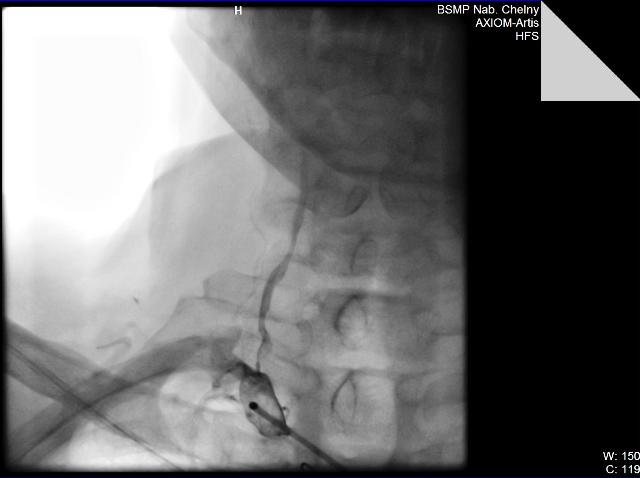

06.09.11. г. Выполнена ангиография ветвей дуги аорты, почечных артерий.

Диагноз: Генерализованный атеросклероз. Атеросклероз брахиоцефальных артерий. Стенозы внутренних сонных артерий слева 60%, справа - 50%, устья позвоночной артерии справа 70%. Сосудистая мозговая недостаточность II ст. Атеросклероз висцеральных ветвей аорты. Стеноз почечной артерии слева 70%. Синдром вазоренальной гипертензии. Синдром Лериша. Стенозы ОПА 85%, НПА 75% справа. Окклюзия НПА слева. Облитерирующий атеросклероз артерий нижних конечностей. Бедренноподколенное шунтирование справа в 1997 г.(шунт окклюзирован). Стеноз ОБА 60%, окклюзия ПБА, ПКА, берцовых артерий правой нижней конечности. Стенозы ОБА – 65%, ГБА 50%, ПКА 60%, окклюзия ПБА, берцовых артерий левой нижней конечности. ХАН нижних конечностей III степени.

06.09.11. БСМП г. Набережные Челны выполнено одномоментное стентирование устья правой позвоночной артерии, левой почечной артерии